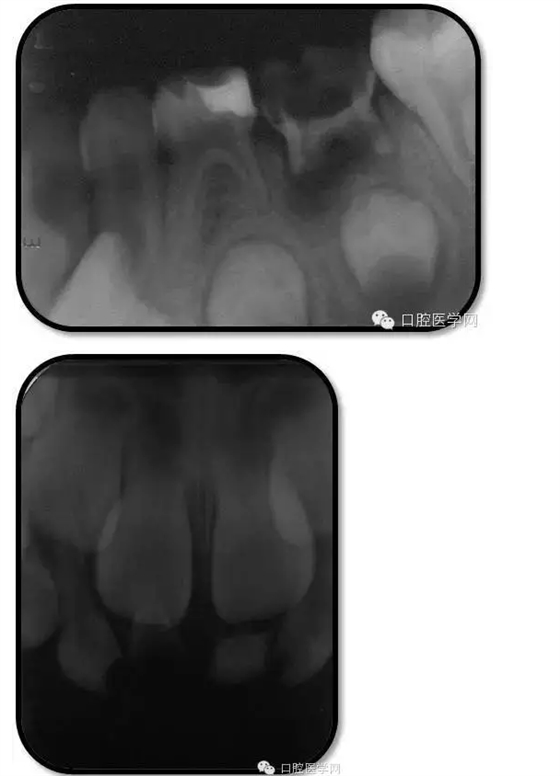

臨床檢查: 75OL齲洞, 舌側(cè)牙體完全劈裂斷端齊齦,探及大量軟化腐質(zhì)。頰側(cè)牙齦紅腫見瘺管,擠壓大量溢膿。叩(±),不松動(dòng)。X線:75根管空虛,牙根吸收約1/2,根尖周及根分歧大面積透射影,35發(fā)育4期,骨硬板尚連續(xù);51殘根,唇側(cè)牙齦瘺管,叩(±),不松動(dòng)。X線:51牙根吸收約1/2,根尖周低密度影。

85O、84DO充填體邊緣不密合,叩(±),不松動(dòng)。84頰側(cè)牙齦略紅腫。X線:84遠(yuǎn)中根及髓室底完全吸收,根分歧透射影,近中根內(nèi)側(cè)見外吸收,44上方骨硬板連續(xù)。85近中根完全吸收,髓室底吸收,根分岐透射影,遠(yuǎn)中根管內(nèi)見根充影像。45發(fā)育4期,骨硬板連續(xù)。

85O、84DO充填完好,邊緣密合,叩(-),不松,齦無紅腫。X線:84、85根分歧透射影,44、45骨硬板連續(xù),恒牙胚上方骨板厚約2-3mm。75帶環(huán)絲圈式間隙保持器完好,無松動(dòng),無咬合不適。64MO中齲。 64MO中齲去腐凈,自酸蝕,SEBOND,樹脂充填。 口腔衛(wèi)生宣教,囑3個(gè)月后復(fù)診。

1、根分歧處病變姑息保留牙的治療及轉(zhuǎn)歸。 75牙體缺損過大,根分岐大面積透射影并累及根尖周。故拔除后間隙保持。84、85初診時(shí)已做過根管治療,有繼發(fā)齲,牙根吸收較多,可見大面積的根分歧病變,但根尖無病變,考慮44、45表面骨硬板連續(xù),故只對(duì)患牙進(jìn)行了繼發(fā)齲充填治療,姑息保留。3個(gè)月復(fù)查時(shí),85O、84DO充填完好,邊緣密合,叩(-),不松,齦無紅腫。7個(gè)月復(fù)查時(shí)85O、84DO充填完好,邊緣密合,叩(-),不松,齦無紅腫。X線:84、85根分歧透射影,44、45骨硬板連續(xù)。 回顧整個(gè)治療過程,應(yīng)定期復(fù)查84、85姑息保留牙,且間隔時(shí)間不宜過長(zhǎng)。觀察根分歧病變的恢復(fù)情況,一旦發(fā)現(xiàn)恒牙胚受累及,則需采取積極措施。

2、75OL、85O、84DO發(fā)生根尖及根分歧病變?cè)?追溯75OL、85O、84DO就診之前病史,84是因慢性根尖周炎1年前行根管治療,治療當(dāng)時(shí)根充滿。75、85因慢性牙髓炎1年前行根管治療,治療當(dāng)時(shí)根充滿。這幾個(gè)牙當(dāng)時(shí)牙體缺損均較大,未行預(yù)成冠修復(fù),隨后充填體脫落,發(fā)生繼發(fā)齲,患兒1年一直未定期復(fù)診,導(dǎo)致口腔內(nèi)感染通過冠方造成根分歧和根尖的炎癥。所以總結(jié)以上,對(duì)于大面積齲壞牙根管治療后應(yīng)定期復(fù)查,并行預(yù)成冠修復(fù)。